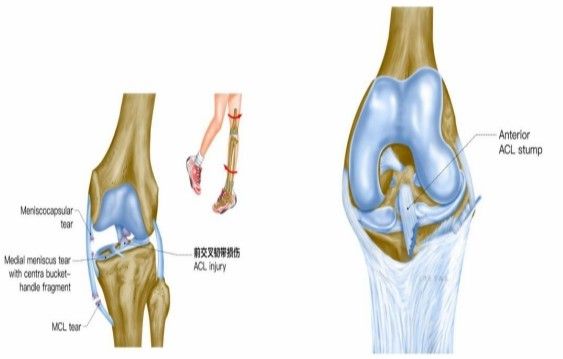

歐洲杯預選賽小組賽中,被譽為“歐洲金童”年僅20歲的運動員加維,右膝交叉韌帶撕裂,面臨賽季報銷+無緣歐洲杯的痛苦。在運動損傷中,“韌帶撕裂”是一個出現頻率非常高的詞,無論是運動員或者是普通人,在生活和運動中都可能會遭遇“韌帶撕裂。”

我院骨科三病區近期收治了4名膝關節交叉韌帶損傷患者。25歲的齊先生,因打籃球時不慎扭傷左膝,致右膝腫痛,遂來我院治療;30歲趙先生酷愛足球,扭傷右膝關節來我院就診;50歲的張先生、42歲劉先生因騎車滑倒摔傷、膝關節腫痛不適、活動受限,收治入院。骨科三病區李鵬主任團隊詳細查體以及完善影像學檢查后進行診斷:幾位患者共同診斷均有“前交叉韌帶損傷”,不同程度合并有“半月板損傷”、“股骨軟骨損傷”、“內側副韌帶斷裂”。

致傷機制

單純前交叉韌帶損傷可發生于非負重條件下膝強力過伸時(如用力踢時未遇到抵抗),或小腿固定、暴力使股骨向后時。單純前交叉韌帶損傷少見,多合并脛側副韌帶、半月板的損傷,此三結構的復合傷在膝部韌帶損傷中最為常見(占52%)。損傷多發生于韌帶中部(占 72%),少數發生于股骨附著點撕脫骨折 (18%)或脛骨附著點撕脫骨折(4%)。損傷后關節內出血、疼痛、活動受限、前抽屜試驗陽性。